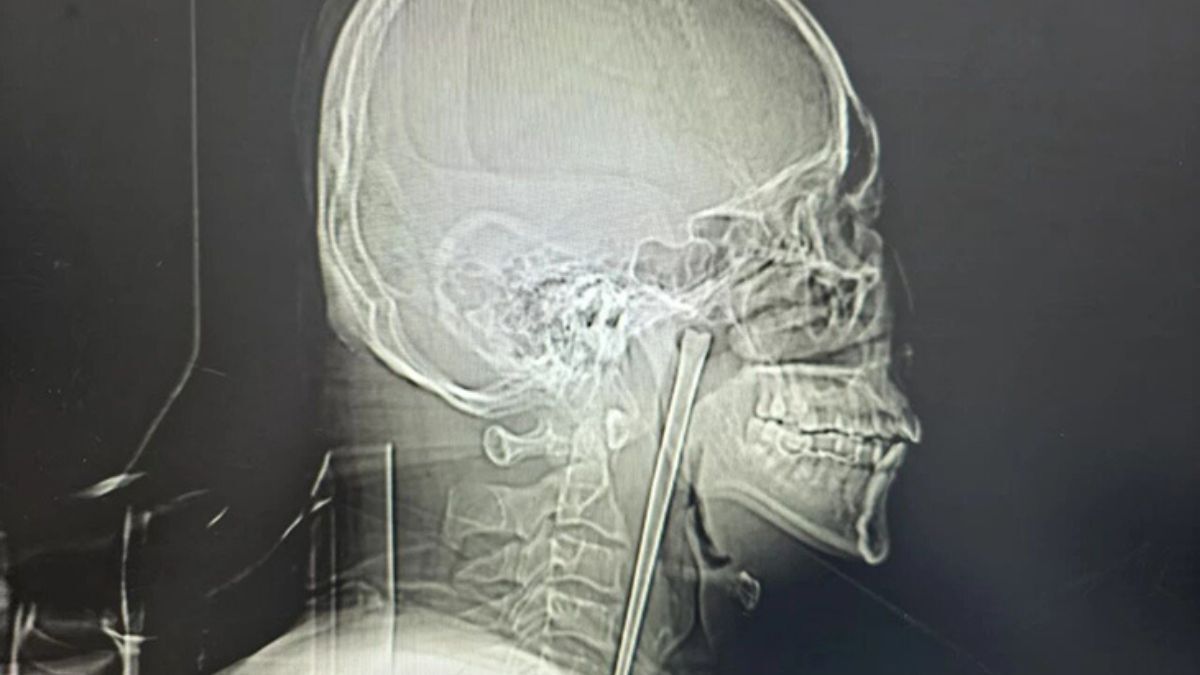

За інформацією джерела, 46-річний пацієнт звернувся до лікарні зі скаргами на сильний біль у горлі та відчуття стороннього предмета в ньому. Після рентгену лікарі виявили довгий металевий стрижень, що застряг у горлянці.

Після обстеження лікарі провели видалення стороннього предмета з тіла чоловіка через ротову порожнину без розрізів на шиї.